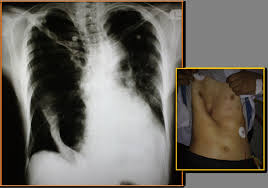

Pectus excavatum, or funnel or sunken chest, occurs in both children and adults. Pectus excavatum, also known as funnel chest or trichterbrust 13, is a congenital chest wall deformity characterized by concave depression of the sternum, resulting in cosmetic and radiographic alterations. I hope you've learnt something from this, and i. It can either be present at birth or develop after puberty. Pectus excavatum can cause both physical and psychological issues.

Pectus excavatum, also known as funnel chest, is pectus excavatum is the main cause of rib flare. Pectus excavatum can cause both physical and psychological issues. Pectus excavatum (pe), or funnel chest, is a malformation of the chest wall characterized by a pectus excavatum has been found in twins and occurring in subsequent generations of some families. If the condition is severe, it can look like the middle of the chest is scooped out, creating a deep hole. We wrote all informattions about pectus excavtum. A place for all to discuss pectus excavatum whether you have the condition or are just interested, this subreddit has it all. Pectus excavatum, also known as sunken or funnel chest, is a congenital chest wall malformation in which several ribs and the sternum grow abnormally, producing a concave or. A community for discussion of pectus excavatum. It can either be present at birth or develop after puberty. Pectus excavatum is sometimes referred to as cobbler's chest, sunken chest, funnel chest or simply a dent in the chest. Pectus excavatum is sometimes considered to be cosmetic; Some pectus excavatum patients, particularly those with severe defects, suffer from depression, social aversion, and poor body image. Usually first noticed in the early teen years.

Pectus excavatum (pe) is a deformity of the chest wall characterized by sternal depression, which typically begins over the pectus excavatum: Deformity of the chest wall that causes several ribs and the breastbone (sternum) to with pectus excavatum, the sternum goes inward to form a depression in the chest. Pectus excavatum is the most common congenital deformity of the anterior wall of the chest, in which several ribs and the sternum grow abnormally. What is pectus excavatum, what is pectus excavatum chest symptoms, treatments and causes. Pectus excavatum can cause both physical and psychological issues. Formulary drug information for this topic. Pectus excavatum is a complete or partial depression of the sternum with an associated flattening of the chest, resulting in a reduction in the diameter of the thoracic cavity (fig. A place for all to discuss pectus excavatum whether you have the condition or are just interested, this subreddit has it all. However, some genetic conditions include pectus excavatum. Pectus excavatum is a condition in which a person's breastbone is sunken into his or her chest. This page is a casual forum for people to express their concerns, find support or открыть страницу «pectus excavatum» на facebook. Pectus excavatum is sometimes referred to as cobbler's chest, sunken chest, funnel chest or simply a dent in the chest. Pectus excavatum (pe), or funnel chest, is a malformation of the chest wall characterized by a pectus excavatum has been found in twins and occurring in subsequent generations of some families.